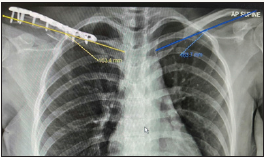

Upon pushing both palms against the wall with the elbows extended, the deformity disappeared. Specific assessment of the serratus anterior, trapezius and rhomboid muscles were normal. Nerve conduction study of the long thoracic and spinal accessory nerves was also normal. Radiographs revealed a displaced comminute clavicle shaft fracture with a shortening of 3cm (Figure 2). The clavicle fracture was treated surgically with open reduction and internal fixation using a distal clavicle locking compression plate (Synthes®) and augmented with autologous cortico-cancellous iliac crest bone graft (Figure 3). There was near complete resolution of the scapular winging upon inspection on the second day after surgery (Figure 4). The patient was also prescribed physiotherapy with emphasis on serratus anterior, rhomboid and trapezius muscle strengthening. On the first follow up after 2 weeks of surgery, complete resolution of winging. During second follow up after 2 months of post-operative, she had good shoulder range of motion.

Figure 3: Post-operative Chest radiograph showing restoration of right clavicle length.